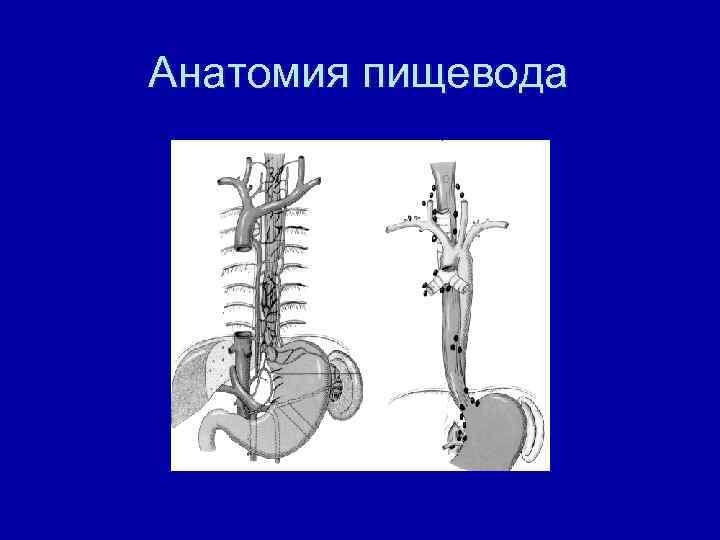

Анатомия пищевода